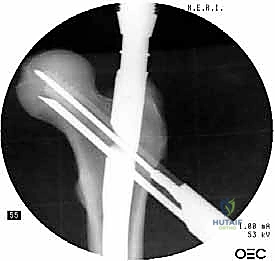

2. الرد المغلق (Closed Reduction)

باستخدام جهاز الأشعة السينية المرئية المستمرة (C-Arm Fluoroscopy) داخل غرفة العمليات، يقوم الدكتور هطيف بإعادة العظام المكسورة إلى محاذاتها التشريحية الصحيحة عن طريق الشد والتدوير الخارجي للساق، وكل ذلك يتم مراقبته على الشاشة بدقة متناهية.

5. تثبيت عنق ورأس الفخذ (المسمار الرأسي)

من خلال ذراع توجيه متصلة بالمسمار الرئيسي، يتم إحداث ثقب في عنق ورأس عظمة الفخذ. يتم إدخال المسمار الرأسي (Cephalic Screw) السميك ليمسك برأس الفخذ بقوة ويسحبه نحو المسمار الرئيسي، مما يضغط الكسر (Compression) ويحفز التئام العظام بسرعة.